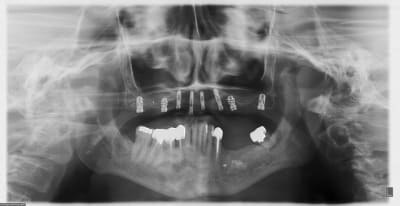

allez, dans ma série, "je remets des sujets" je vous donne quelques nouvelles de ce cas

la raison et vos conseils me sont revenus, j'ai posé hier 2 implants supplémentaires en 17 et 27 (sans les facturer à mon patient)

ce qui me frappe, tout de même, avec les quelques radios prises, c'est la cicatrisation osseuse au niveau de ceux en 15 et 25 (cf panos jour de la pose/3mois/4mois et les "zooms" pose/4mois)

la nature est parfois très sympa...;-)

en 17, non pas dans le sinus...à ras, mais pas dans le sinus

Oups, le 2e implant en secteur 1 en partant du fond...

Celui qui est court, avec les spires distales dans le vide, enfin, il me semble...